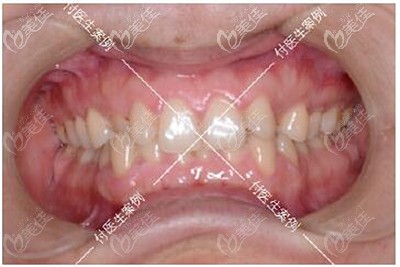

術(shù)前照片:

牙齒診斷:牙齒擁擠不齊+深覆合+單顆反頜+下頜方形牙弓

大家可能看我的牙齒圖片覺得我的問題不大,但其實我之所以下定決定要去做矯正的原因是因為我的咀嚼功能已經(jīng)完全受影響了,而且上下牙咬合導(dǎo)致我睡覺經(jīng)常磨牙、連帶著下巴后縮也常常讓我覺得自己像“凸嘴”...

深覆合牙齒矯正前后牙齒效果對比